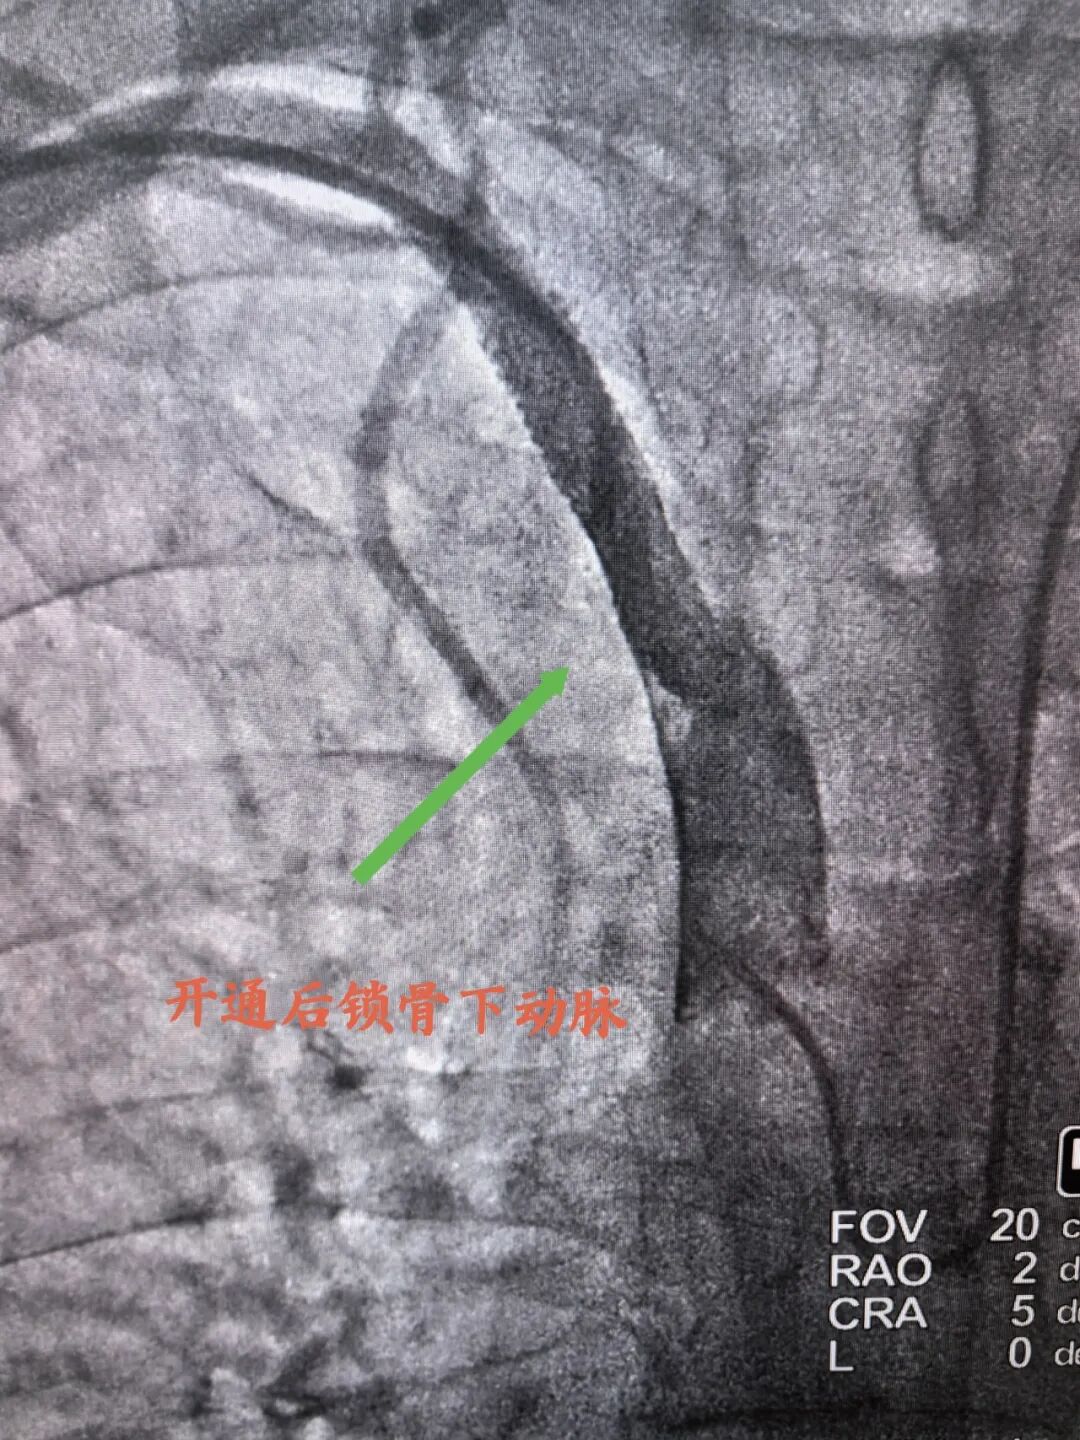

开通后锁骨下动脉

造影结束后,介入诊疗组经过讨论后,考虑患者不能长时间卧床,不适合穿刺股动脉,故选择双侧桡动脉,“一站式”开通闭塞锁骨下动脉及冠脉介入治疗,术中成功为患者开通闭塞右锁骨下动脉,并成功完成冠脉两处病变介入治疗,整个手术一气呵成,过程不到3小时。术后患者测量右上肢血压达120/70mmHg,他惊叹道:“我胸闷、气短好多了,右手能摸到脉了”。